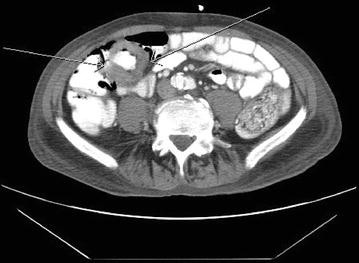

In November 2011, he developed blood streaked bowel movement and severe anemia with hemoglobin of 5.9 g/dL. He underwent CT scan of abdomen and pelvis and colonoscopy, and was found to have a 3-cm mass in the proximal ascending colon (Fig. 1). The biopsy showed metastatic SCC (Fig. 2). Immunohistochemical study showed the tumor was strongly positive for CK 5/6, with foci of weak staining for p63 and negative staining for CK20 or CDX2, which was most consistent with a metastatic lesion rather than a primary colorectal carcinoma. He subsequently received palliative radiation (3000 cGy) to the ascending colon cancer with improvement of anemia, and remained transfusion independent for more than 3 months. In January 2012, he also received palliative radiation for brain metastasis. He was offered palliative chemotherapy but he refused. He entered hospice in May 2012, and passed away shortly afterwards.